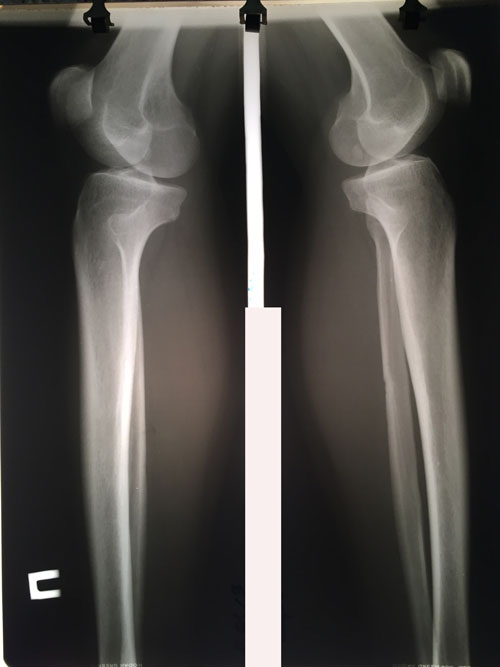

Дата операции - 08.01.2019г.

Дата снятия аппаратов - 26.04.2019г.

Срок сращения - 105 дней.